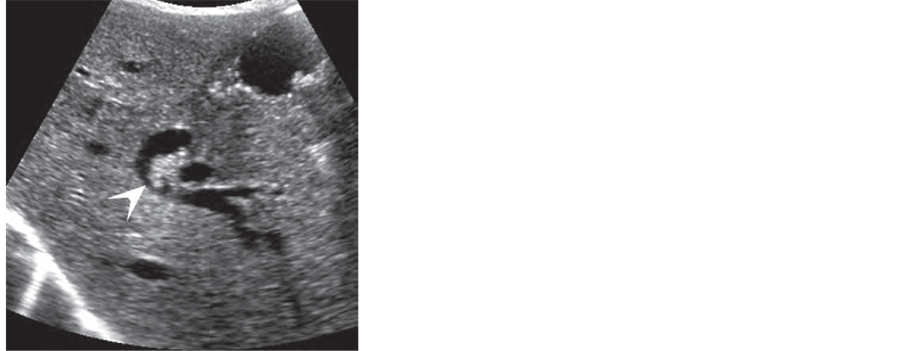

Pitfalls in the diagnosis of CBDS include blood clot (hemobilia) (Figure 4(a) & Figure 4(b)), papillary tumors, and occasionally biliary sludge; none of these will

Figure 4. Hemobilia: spectrum on sonography. (a) Echogenic blood clot (arrow head) within a dilated duct, after insertion of biliary drainage catheter. Biliary obstruction was caused by pancreatic tumor; (b) Echogenic clot in the common hepatic duct after liver biopsy [24] .